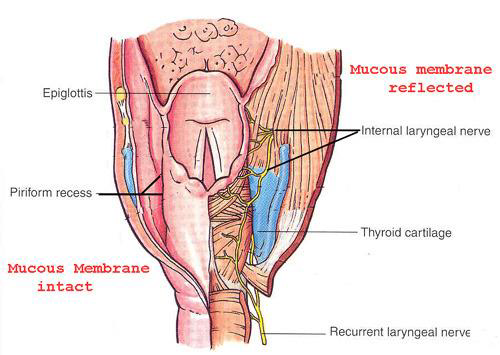

Laryngopharynx

Sensor:CN X

- Epiglottis

- Piriform recess

- (medial) larynx;

- (lateral) thyroid cartilage

- (posterior) Inf. pharyngeal constrictor m.

Nerve

- Sup. laryngeal n.

- Internal br.(Internal laryngeal n.)

- Sensor

- 穿過 Thyrohyoid ligament

- Recurrent laryngeal n.

- Inf. laryngeal a.伴行

- 過Cricothyroid joint改叫Inf. laryngeal n.